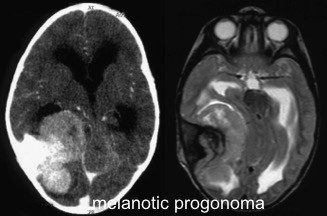

le progonome mélanotique

synonyme : PNET mélanotique

c’est une tumeur maligne du nourrisson, le plus souvent à peau sombre, qui se développe à partir d’une fontanelle et progresse rapidement. la chirurgie la plus complète possible est nécessaire avec nécessité de reconstruction durale et osseuse ; la chimiothérapie des PNET montre une efficacité limitée sur les progonomes.

pour en savoir plus : [Melanotic neuroectodermal tumors of infancy: Current state of knowledge].

5 le progonome mélanotique, reclassé avec les tumeurs embryonnaires de type PNET est une tumeur rare du jeune nourrisson, souvent à la peau foncée, et se développe typiquement à partir d’une fontanelle, de manière rapide voire explosive.